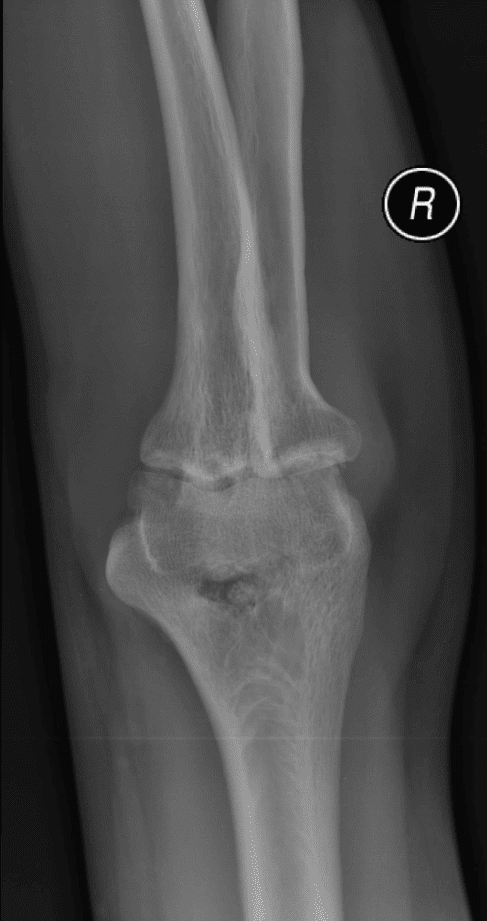

U sụn màng hoạt dịch

» Thông tin: Nữ giới – 32 tuổi.

» Lâm sàng: Đau khuỷu tay 2 năm.